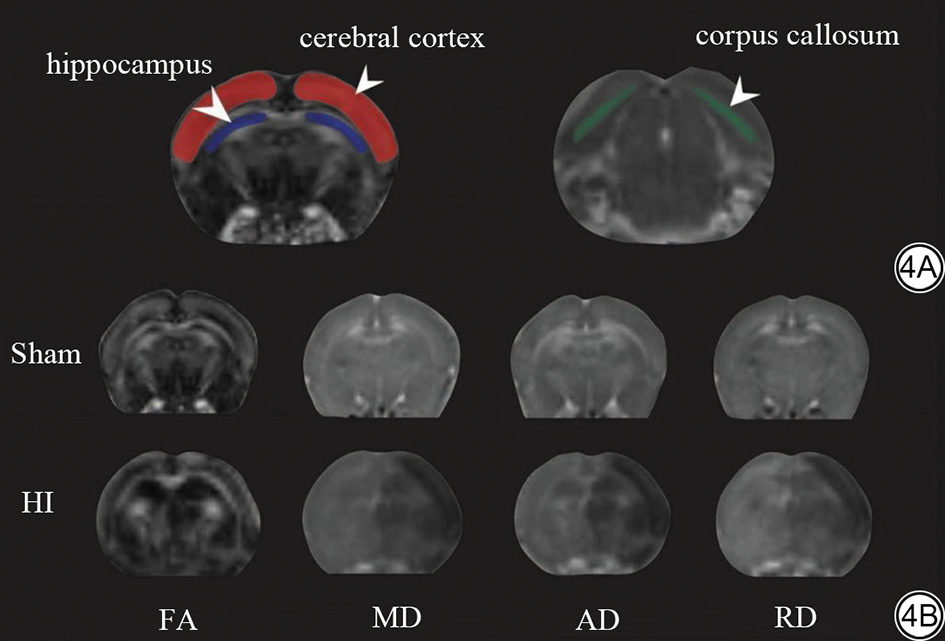

大鼠脑部特定区域的白质微观结构变化如图4所示。纵向比较显示,与Sham组相比,HI组三个脑区的FA值自术后呈现随时间持续下降的趋势,至术后第7天降至最低;而MD、AD及RD值则随病程进展呈持续升高趋势。大脑皮层作为代表性区域,其损伤模式尤为典型:其FA值自术后第1天起降低(P<0.001),并随时间的推移呈进行性下降,至第7天时差异最为显著(0.269±0.038 vs. 0.154±0.015,P<0.001)。相应的,其MD、AD和RD值亦从第1天开始持续升高,于第7天达到峰,详见图5

图4  大鼠脑部特定区域与白质微观结构变化。4A:大鼠脑区ROI勾画示意图。左侧面板中红色区域标示双侧大脑皮层,蓝色区域标示双侧海马(白色箭头);右侧面板中绿色区域标示胼胝体。4B:HI术后24 h各组代表性DTI参数图,包括FA、MD、AD及RD。ROI:感兴趣区;DTI:扩散张量成像;FA:各向异性分数;MD:平均扩散系数;AD:轴向扩散系数;RD:径向扩散系数;HI:缺氧缺血性脑损伤;Sham:假手术组。

Fig. 4  Changes in specific brain regions and white matter microstructure in rats. 4A: Schematic diagram of ROI delineation in rat brain regions. In the left panel, the red areas indicate the bilateral cerebral cortex, and the blue areas indicate the bilateral hippocampus (white arrows); in the right panel, the green area indicates the corpus callosum. 4B: Representative DTI parameter maps of each group 24 h after HI surgery, including FA, MD, AD and RD. ROI: region of interest; DTI: diffusion tensor imaging; FA: fractional anisotropy; MD: mean diffusivity; AD: axial diffusivity; RD: radial diffusivity; HI: Hypoxic-Ischemic brain injury; Sham: Sham operation.